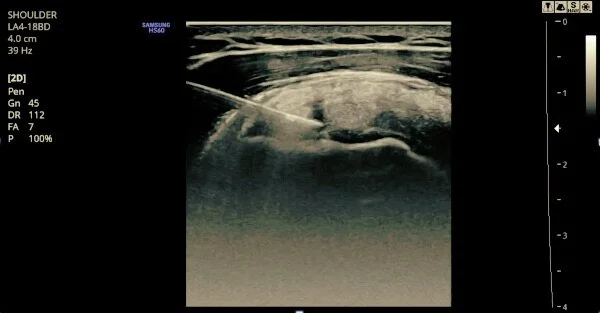

Platelet-Rich Plasma

Platelet-rich plasma (PRP) is widely used in orthopedics and sports medicine as an effective treatment for soft tissue injuries and early-stage osteoarthritis. PRP contains an elevated concentration of platelets (typically 6-8 times the body’s normal concentration), which are used to stimulate repair of injured tissue, reduce inflammation, and restore function.